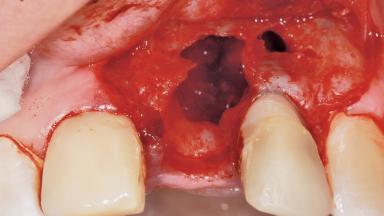

Late Placement of an Implant in a Maxillary Left Central Incisor Site

Bone Augmentation Horizontal|Staged

Bone Volume Deficient horizontally, requiring prior grafting

Augmentation Materials Xenogenous|Membrane

Soft Tissue Grafting Simultaneous